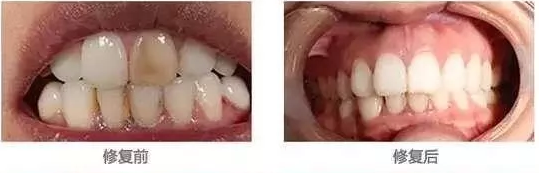

3、牙齒貼面:牙齒貼面美白,其實就是使用陶瓷貼面、樹脂貼面等貼在牙齒表面,遮蓋變色的牙齒。

適用于難以通過漂白劑達到較好的美白效果的牙齒,如四環(huán)素牙等,但存在打磨后釉質變薄的問題,如果醫(yī)生技術不好,較容易磨損脫落,費用相對來說也比較貴。